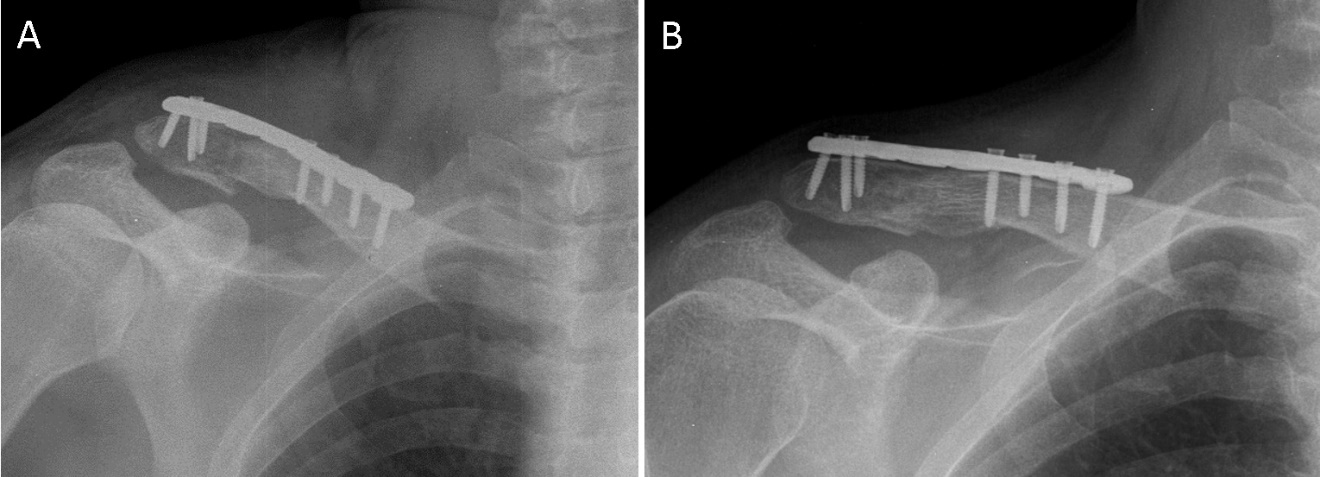

The bone fragments were anatomically reduced, and a custom-made plate was positioned on the superior surface of the clavicle. It was temporarily held in place with Kocher clamps and then fixed with seven locking screws (Figure 3). Under fluoroscopic guidance, proper alignment was confirmed, and any residual displacement was corrected. Hemostasis was achieved using electrocoagulation. The wound was closed in layers with interrupted sutures, covered with a sterile dressing, and the limb was immobilized in a sling. Estimated intraoperative blood loss was 100 mL.

Postoperative radiographs confirmed anatomical alignment of the fracture fragments and stable osteosynthesis using the developed plate and screws (Figure 4A). The bone and implant positions were satisfactory. The patient followed a standard orthopedic regimen, including sling immobilization for 14 days. From day 15, supervised horizontal shoulder movements were initiated, and by the fourth postoperative week, gradual active shoulder exercises were introduced as tolerated.

At the two-month follow-up, radiographs showed maintained reduction, stable osteosynthesis, and radiological signs of fracture healing (Figure 4B). The patient reported no pain or discomfort, and physical examination revealed no asymmetry of the shoulders and a well-healed postoperative scar without inflammation.